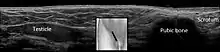

Cryptorchidism on scrotal ultrasound | |

In the minority of cases with bilaterally nonpalpable testes, further testing to locate the testes, assess their function, and exclude additional problems is often useful. Scrotal ultrasound or magnetic resonance imaging performed and interpreted by a radiologist can often locate the testes while confirming absence of a uterus. At ultrasound, the undescended testis usually appears small, less echogenic than the contralateral normal testis and usually located in the inguinal region. With color Doppler ultrasonography, the vascularity of the undescended testis is poor.